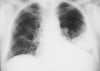

Правосторонняя нижнедолевая пневмония

Такая рентгенография грудной клетки показывает наличие инфильтрата, который не затемняет правую границу сердца (т.е., признак "утраты контура" отсутствует). Поскольку признак "утраты контура" развивается, когда 2 примыкающие структуры имеют сходную рентгенконтрастность, доля легкого, пораженная этим инфильтратом, не соприкасается с правой границей сердца, т.е. является правой нижней долей.